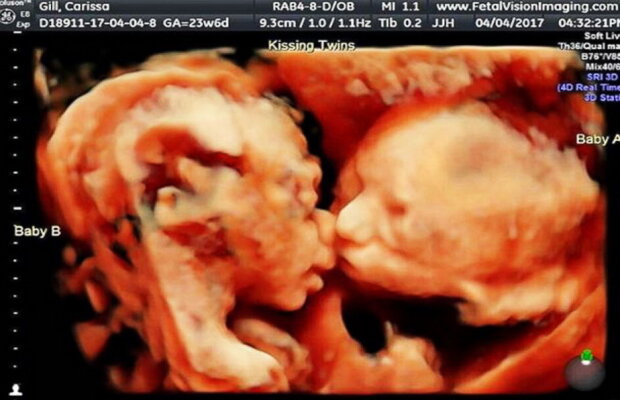

Gemene surprinse la ecografie în timp ce se sărutau în burtica mamei